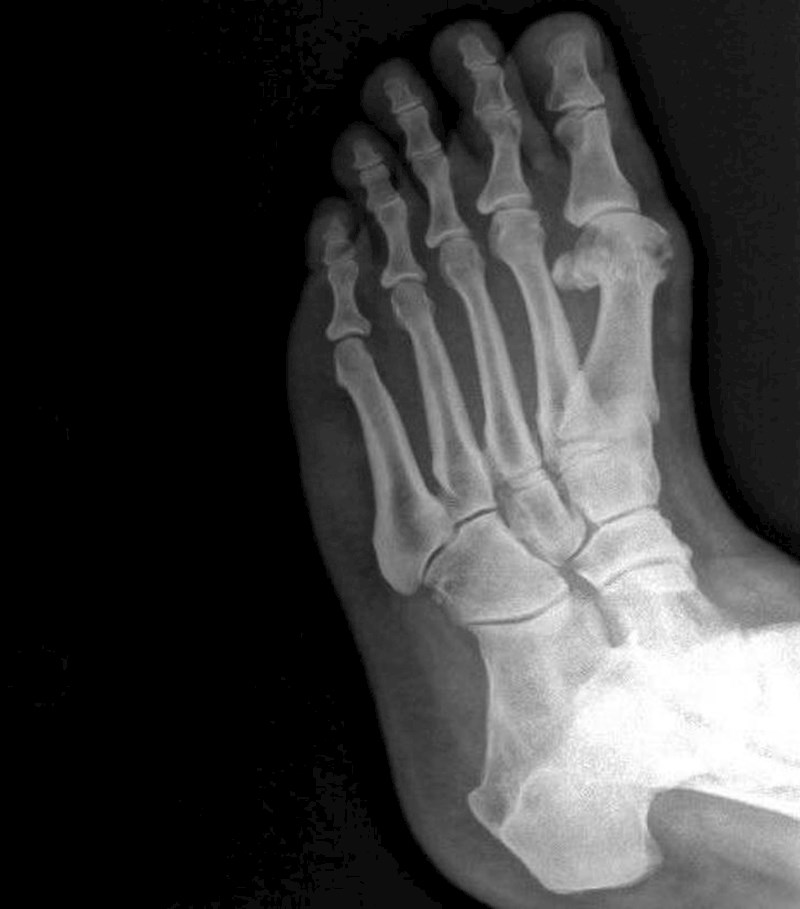

Snimka stopala sa 6 prstiju